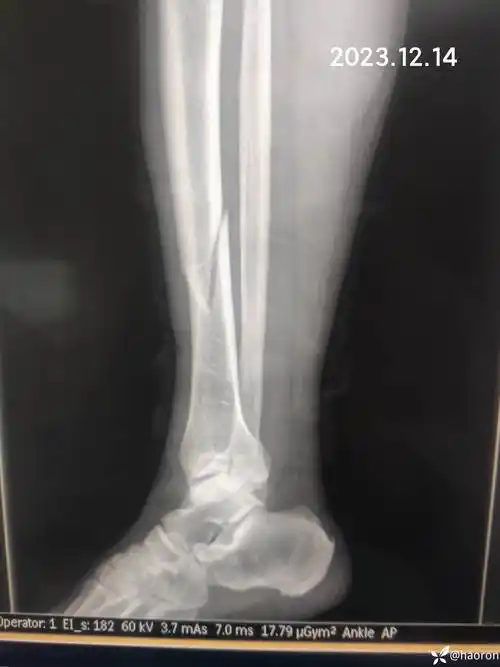

胫腓骨骨折保守治疗一月复查下步处理